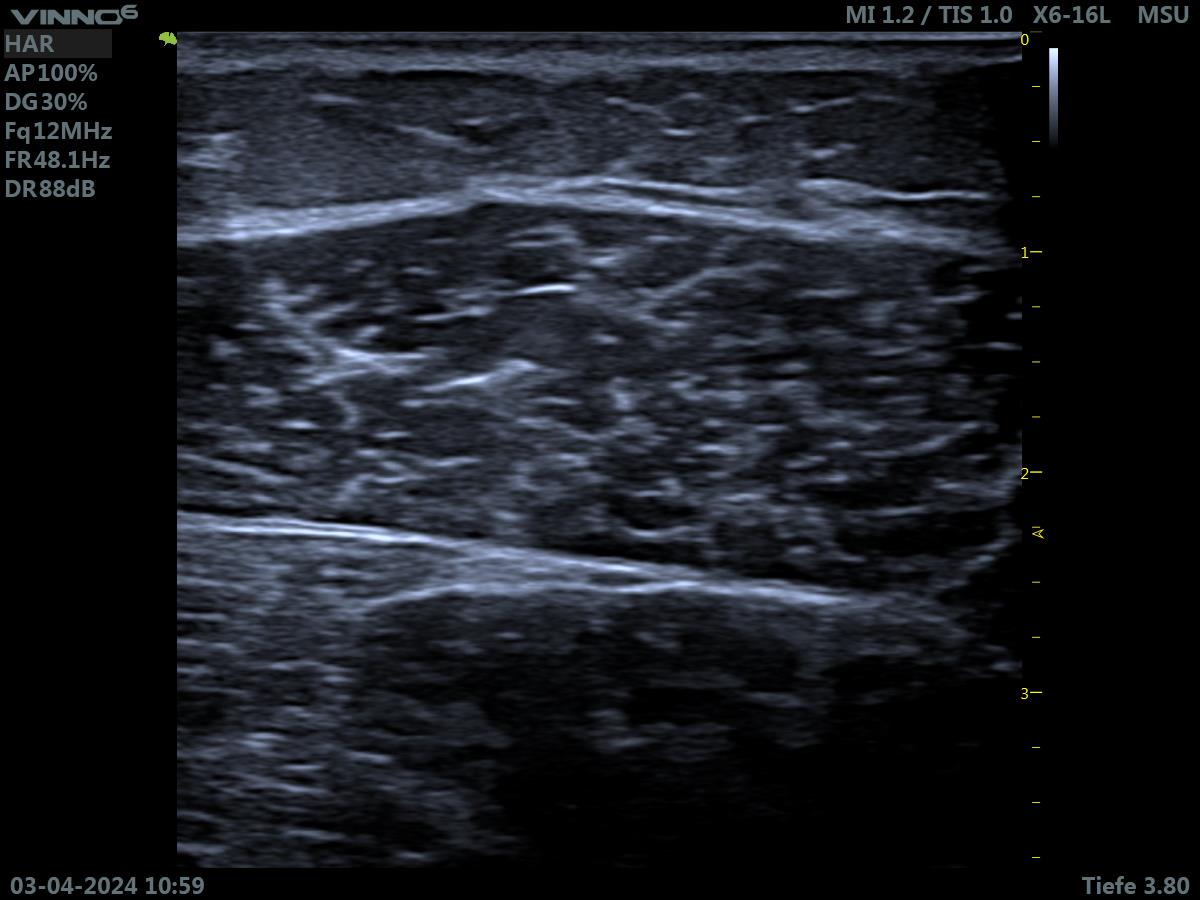

Muskeln im Ultraschall

Mittels Ultraschall können wir Verletzungen und bestimmte krankhafte Veränderungen im Muskel erkennen.

Gesunder Muskel

Pathologie am Muskel

Dieses Ultraschallbild zeigt einen durch Polyneuropathie geschädigten Muskel.